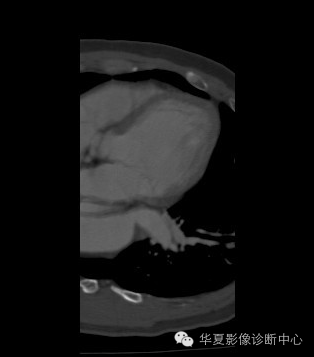

| 影像表现及分析: | 影像表现:定位左下叶;左下叶体积缩小,整体密度增高,支气管分布正常,其内见血管增多,但是走形正常,未见杂乱、迂曲的血管影;血管连向肺门下方软组织密度结节灶,结节与主动脉分界不清,增强后,见降主动脉发出异常粗大血管供血整个左下叶,左下肺动脉细小。 |

异常体动脉供应正常下肺基底段完整含义为起源于降主动脉的异常动脉供应下肺基底段,而基底段支气管树和肺实质正常,同时基底段肺动脉缺如或狭窄【大部分缺如(完全型),部分狭窄(不完全型)】;95%以上累及左下肺,因此也称为异常体动脉供应正常左下肺基底段。 病因尚未明确,可能是胚胎发育时期供应肺芽的背主动脉原始小分支退化不全,与肺实质形成异常连接,并影响肺动脉与肺血管床连接而导致此部位肺动脉发育不良,而支气管、肺组织的发育未受影响。本病的病理生理基础为左向左的分流,体动脉供应的肺组织充血,体循环的高压可增加肺血管床的压力和左心负荷,同时也增加肺循环量和压力而增加右心负荷,导致各种临床症群。本病可无临床症状,部分患者可有咯血、呼吸道感染、呼吸困难、充血性心力衰竭。 影像表现:左肺下叶体积缩小,整体密度稍增高,支气管树走形、分布正常,血管增多、稍增粗;增强后显示左下肺动脉幼小,甚至不发育;下叶由主动脉发出的粗大血管供血。 |